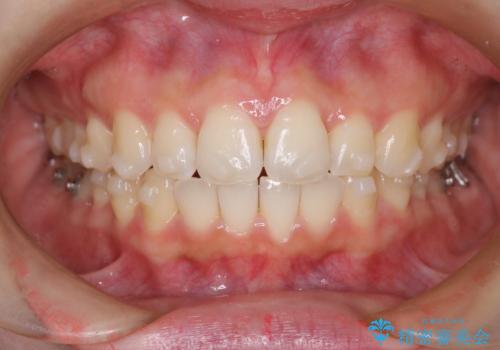

【インビザライン】前歯が出てるのを治したい

- 前歯の凸凹と前突を主訴に来院されました。

インビザラインにて治療をおこない、歯並びを改善することができました。